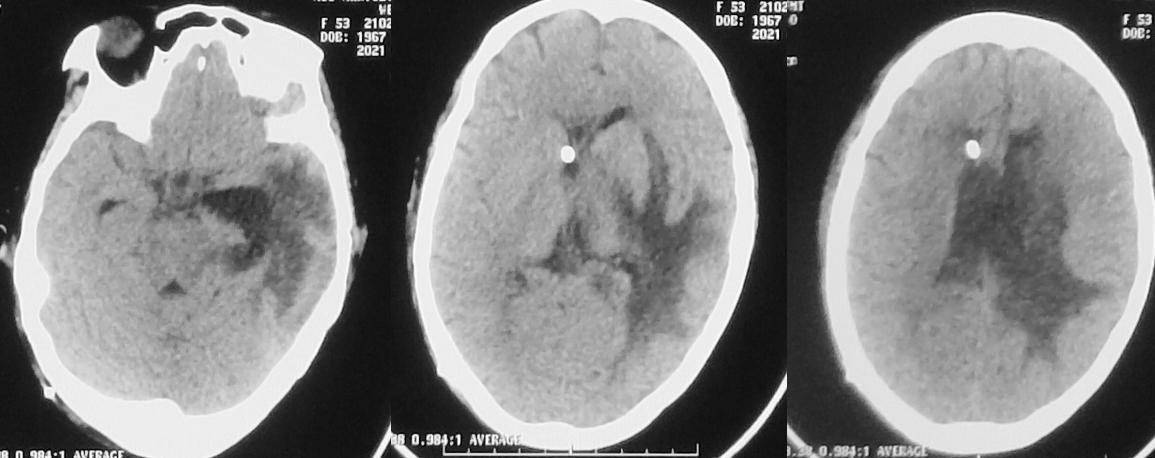

入院当天,患者出现恶心、呕吐数次,意识变差呈昏睡状态,强刺激才能睁眼。复查头颅CT见左侧丘脑病变增大,周围水肿明显,脑室扩张( 图-3 ),医生给予脑室穿刺外引流术。

图-3: 2020年11月21日头CT